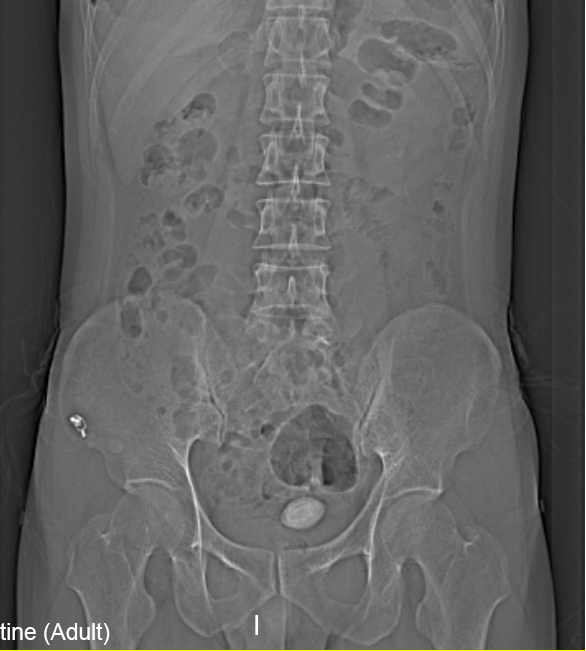

“医生我尿不出,尿里有血,快帮帮我”。近日,在温州市人民医院泌尿外科门诊一位男青年向坐诊的黄来剑主任求助,经验丰富的黄主任在了解基本病情后,特意触摸了一下患者耻骨上区,并嘱咐患者进行泌尿系平片检查,结果在意料之中也出乎意料之外。意料之中的是患者诊断如黄主任所想膀胱结石进入尿道卡住了,意料之外的是结石直径达到了35mm,像蛋黄大小了,这对年轻患者来说并不常见,堵住了尿道,把患者痛的够呛。

▲患者影像学检查